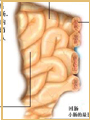

疾病早期,因病理的可逆性,肉眼觀解剖學上很少器質性改變。隨疾病發展病理學變化逐漸明顯,肉眼可見肺過度充氣及肺氣腫,肺柔軟疏鬆,可合併有肺大泡。支氣管及細支氣管內含有粘稠痰液及粘液栓。支氣管壁增厚、黏膜腫脹充血形成皺襞,粘液栓塞局部可發現肺不張。顯微鏡下的改變比較明顯。即使在輕症的哮喘患者,可見氣道上皮下有肥大細胞、肺泡巨噬細胞、嗜酸性粒細胞、淋巴細胞與嗜中性粒細胞浸潤。哮喘發作期,氣道黏膜下組織水腫,微血管通透性增加,支氣管內分泌物貯留,支氣道平滑肌痙攣,纖毛上皮剝離,基底膜露出,杯狀細胞增殖及支氣管分泌物增加等病理改變。若哮喘長期反覆發作,表現為支氣管平滑肌的肌層肥厚,氣道上皮細胞下的纖維化等致氣道重構和周圍肺組織對氣道的支持作用消失。儘管哮喘的病因及發病機理均未完全闡明,但目前的治療方法,只要能夠規範地長期治療,絕大多數患者能夠使哮喘症狀能得到理想的控制,減少復發乃至不發作,與正常人一樣生活、工作和學習。為使哮喘診斷治療工作規範化,1994年在美國國立衛生院心肺血液研究所與世界衛生組織的共同努力下,共有17個國家的301多位專家組成小組,制定了關於哮喘管理和預防的全球策略(GINA)。中華醫學會呼吸分會也於1993年和1997年議定和修訂了中國的哮喘防治指南,促進了防治水平的提高。